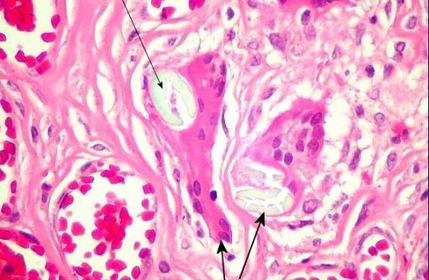

Granuloma de corpo estranho- presença de gigantócitos/células gigantes de corpo estranho como reação à um fio cirúrgico

Gigantócito de corpo estranho- como resposta à um fio cirúrgico (no centro do granuloma), perceba que o gigantócito é uma grande célula multinucleada, formada pela união de macrófagos